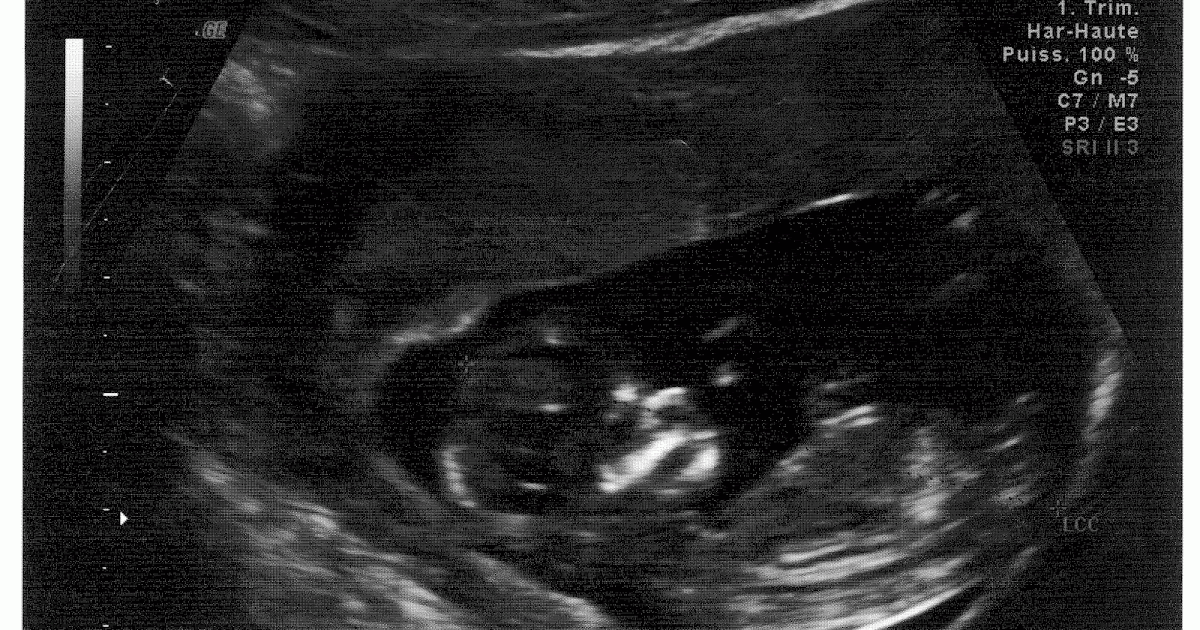

Sarcina Mea Ecografie 12 Saptamani

Ecografie bebe 12 saptamani

Mia spus ca e baietel!Cele mai multe femei nu vor mai avea greturi incepand cu aceasta saptamana Afla ce altceva se va mai intampla cu tine si copilul tau La 12 saptamani de sarcina copilului tau i se dezvolta unghiile si cantareste aproximativ 14 grame Cea mai dramatica dezvoltare a copilului din aceasta saptamana sunt reflexele Degetele copilului se strang si se rasfira, Ecografie 12 saptamani La 12 saptamani de sarcina a fost cea mai emotionanta si mai importanta ecografie pentru mine si pentru sotul meu Pana atunci facusem numai ecografii intravaginale si el nu fusese prezent Mai facusem o ecografie cand am fost internata in spital, dar nici la aceea nu fusese prezent Tot ce vazuse fusesera pozele, unde

Eram nerabdatoare sa te vad pentru prima data La ecografie am aflat ca ai 9 saptamani, de si eu ma programasem pt morfologic semestru 1 Crezand ca deja ai 12 saptamani de cand imi intarziase ciclul In continuare am stari de greata care din pacate tine toata ziua Dar incerc sa ma bucur de sarcina buna seara, am facut azi ecografie, rezultatele sunt in engleza, caci le'am facut in grecia, si as dori o interpretare prima zi a ultimei menstruatii este 9 mai, deci pana acum am 12 saptamani de amenoree azi am facut ecografie, si ca rezultat e cam asa Gestational age GA(CRL)Rempen 622 Saptamana 12 si 13 de sarcina reprezinta momentul cel potrivit pentru morfologia fetala de trimestru I de sarcina, o ecografie care permite sa se dateze inceputul sarcinii, se masoara copilul din varful capului pana la fese, diametrul capului, al stomacului , al femurului si translucenta nucala De asemenea se verifica daca placenta este bine